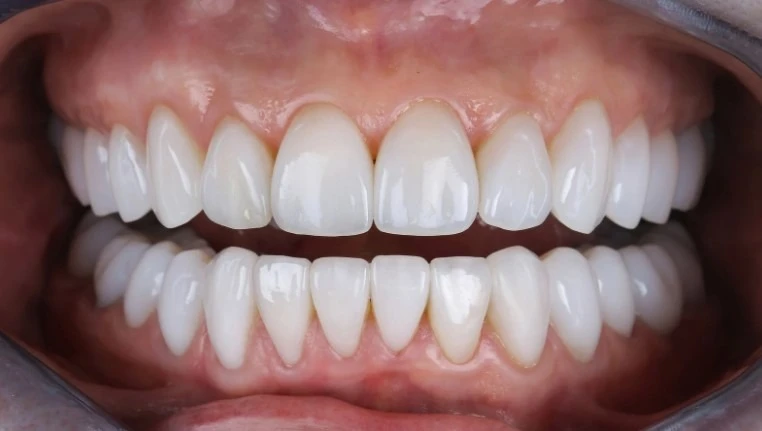

Имплантация тіс қатарының анатомиялық тұтастығын қалпына келтіріп, тамақты толыққанды және сапалы шайнауға мүмкіндік береді. Заманауи технологиялар арқылы қалпына келтірілген тістер табиғи тістерден іс жүзінде ерекшеленбейді, бұл асқорыту жүйесі үшін қауіптерді айтарлықтай төмендетеді.

Benefakta Dental компаниясы әрбір клиникалық жағдайды жеке бейімдеуге ерекше көңіл бөледі. Пациент ем алу үшін жүгінген кезде шайнау функциясын қалпына келтіру мәселесі жан-жақты шешілетініне сенімді бола алады. Сонымен қатар көптеген пациенттер мамандардың тәжірибесімен және нәтижелерімен танысу мүмкіндігіне ие, бұл емдеу кезеңінде дұрыс таңдау жасауға көмектеседі.